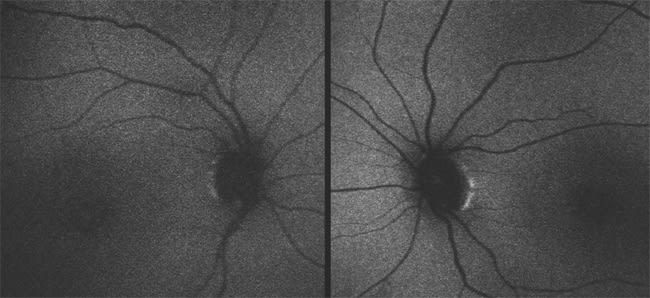

Patient 3 has high hyperopia (+8.00 OU), nystagmus, VA of only LP and a normal-appearing fundus. She was diagnosed at the age of six months because of poor responses to visual stimuli, photophobia and undetectable responses on ERG testing. Fundus photos at 25 years of age are shown in Figure 6, and autofluorescence images are shown in Figure 7.

Figure 7. Autofluorescence images of the same patient as in Figure 6 demonstrate normal autofluorescence, as is typically seen in patients with GUCY2D mutations.

Patient 3 has LCA due to mutations in the GUCY2D (guanylate cyclase) gene. GUCY2D is one of the key enzymes within the phototransduction cascade. Mutations in this gene prohibit reopening of cyclic guanosine mono-phosphate (cGMP)–gated cation channels after photoexcitation, thereby maintaining a state resembling continuous light exposure. Patients with mutations in this gene typically have VA in the LP range, with a few reports of VA up to 20/40.9 In most cases, the fundus remains normal throughout life, although granular pigmentary changes may sometimes develop in the periphery.